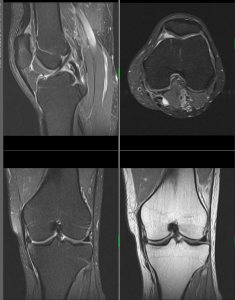

MR muskuloskeletálního systému

Vyšetření ramenního, kolenního, kyčelního, hlezenního kloubu, temporomandibulární (čelistní klouby), MR je suverénní při vyšetření menisků, vazů, chrupavek, svalů,MR dokonce zobrazí zlomeniny, které nejsou viditelné při běžném rentgenovém vyšetření nebo na CT (což je umožněno zejména identifikací edému), průkaz infekcí kostní tkáně (osteomyelitida) a nádorů (metastázy do kostí a kloubů).

Na našem pracovišti provádíme vyšetření mozku, orbit, hypofýzy, krční páteře, hrudní páteře, bederní páteře, kolenního kloubu, ramenního kloubu, jater a pankreatu, MRCP, ledvin a nadledvin, pánve, MR enterografii, MR angiografii intrakraniálních tepen, MR angiografii mozku – venózní, MR angiografii karotid, MR angiografii tepen dolních končetin, MR angiografii renálních tepen a vyšetření ostatních kloubů těla.